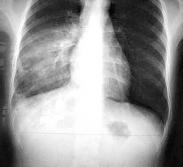

急性嗜酸性粒細胞性肺炎

• 急性嗜酸性粒細胞性肺炎

628健康網為您分享有關急性嗜酸性粒細胞性肺炎的癥狀,急性嗜酸性粒細胞性肺炎的治療方法,急性嗜酸性粒細胞性肺炎的預防...